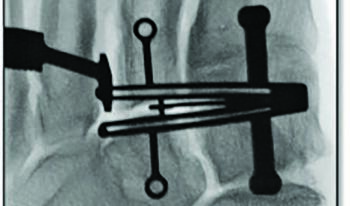

The cut guide keel for this technique interfaces with the second and third TMT, and the cut slots align over the joint spaces in their respective planes. The cannulated outrigger fixation points provide a fluoroscopic visual reference to ensure there is no parallax when determining the guide position at the osseous anatomy. The medial aspect of the cut guide lines up at the lateral border of the medial cuneiform. The surgeon checks the lateral border of the cut guide with C-arm, and inserts a metal marker or fulcrum between the third and fourth metatarsals to delineate the far border of the third metatarsal. These steps and checks reduce the risk of saw blade injury to the medial cuneiform and fourth metatarsal. The goal of the cut guide anatomy is to allow for creation of a continuous angular bone cut at both the metatarsal and cuneiform joint surfaces. This exposes the subchondral bone surfaces to promote arthrodesis similar to the Lapiplasty® (Treace Medical Concepts, Inc.) instrumented triplanar approach at the first TMT.29

Autologous cancellous bone graft may augment arthrodesis in this region. Liberal fenestration of the surfaces facilitates localized bone graft incorporation and helps the joint surfaces interdigitate during bone docking, in my experience. An “up and out – gate-hinge closure” technique reduces the midfoot deformity and the bone gap created by the cuts.1 One performs this technique manually, or assisted with a compressor device, which further stabilizes the reduction and acts as a form of provisional fixation at the lesser TMTs. One applies this device across the third TMT, and fixation is with two parallel threaded olive wires from the lateral aspects of the second and third metatarsals to the medial and intermediate cuneiforms, respectively. The fourth and fifth metatarsals have flexibility at their respective metatarsocuboid joints, which allows for motion back into position without the need to perform an osteotomy or arthrodesis of the lateral column.